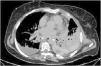

This is the case of a 67-year-old woman admitted to the ICU with refractory distributive shock. The thoracic x-ray (Fig. 1) revealed the presence of a left-sided hydropneumothorax, with a 5 cm apical pleural leave separation and contralateral mediastinal shift (⋆). The CAT scan performed (Fig. 2) revealed the presence of a hydropneumothorax and pleural empyema and periesophageal pneumomediastinum in the lower third of the esophagus (⋆). Thoracic drainage is performed, with the release of air and foul-smelling cloudy fluid containing "abundant bacteria, fat droplets, and fibers suggestive of food remnants." Upon suspicion of esophageal perforation, the new CAT scan performed with the administration of oral contrast (Fig. 3) reveals the presence of contrast extravasation at left lateral margin level of the lower esophagus, consistent with perforation, and contrast passage into the left pleural cavity (⋆). Emergency surgery is eventually performed.